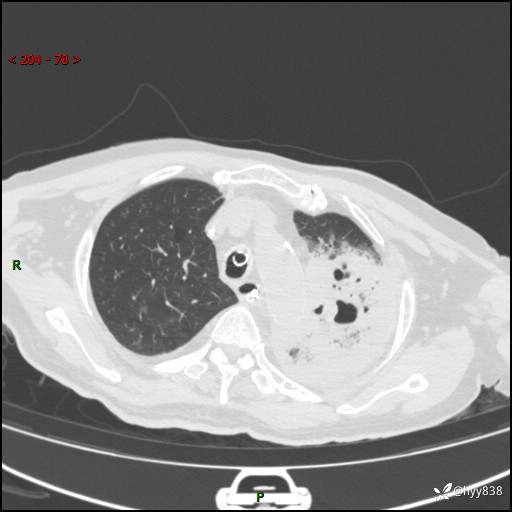

胸部CT平扫(2024.7.24)